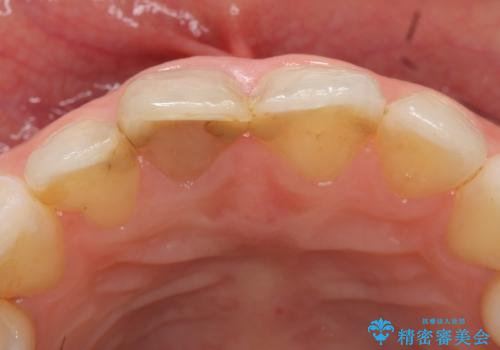

- 右上1番目の歯の変色が気になると来院された方の症例です。

検査の結果、右上1の歯は失活(歯の神経が死んでいること)していたため根管治療を行いました。

その後オールセラミッククラウン(スペシャル)による補綴を行いました。